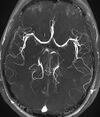

MR angiogram in congenital heart disease

Cardiac MRI is complementary to other imaging techniques, such as echocardiography, cardiac CT, and nuclear medicine. It can be used to assess the structure and the function of the heart.[40] Its applications include assessment of myocardial ischemia and viability, cardiomyopathies, myocarditis, iron overload, vascular diseases, and congenital heart disease.[41]

Magnetic resonance angiography

Magnetic resonance angiography (MRA) generates pictures of the arteries to evaluate them for stenosis (abnormal narrowing) or aneurysms (vessel wall dilatations, at risk of rupture). MRA is often used to evaluate the arteries of the neck and brain, the thoracic and abdominal aorta, the renal arteries, and the legs (called a "run-off"). A variety of techniques can be used to generate the pictures, such as administration of a paramagnetic contrast agent (gadolinium) or using a technique known as "flow-related enhancement" (e.g., 2D and 3D time-of-flight sequences), where most of the signal on an image is due to blood that recently moved into that plane (see also FLASH MRI).[51]

Techniques involving phase accumulation (known as phase contrast angiography) can also be used to generate flow velocity maps easily and accurately. Magnetic resonance venography (MRV) is a similar procedure that is used to image veins. In this method, the tissue is now excited inferiorly, while the signal is gathered in the plane immediately superior to the excitation plane—thus imaging the venous blood that recently moved from the excited plane.[52]